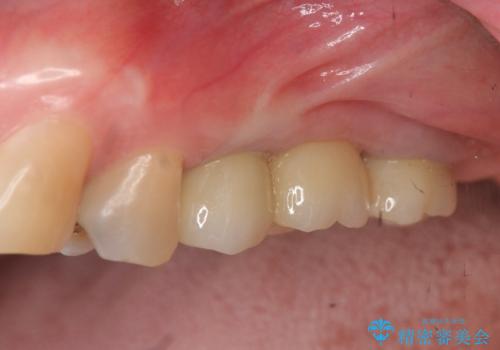

しっかりと噛めるようになったことで、また食事を楽しんでいただくことができるようになりました。